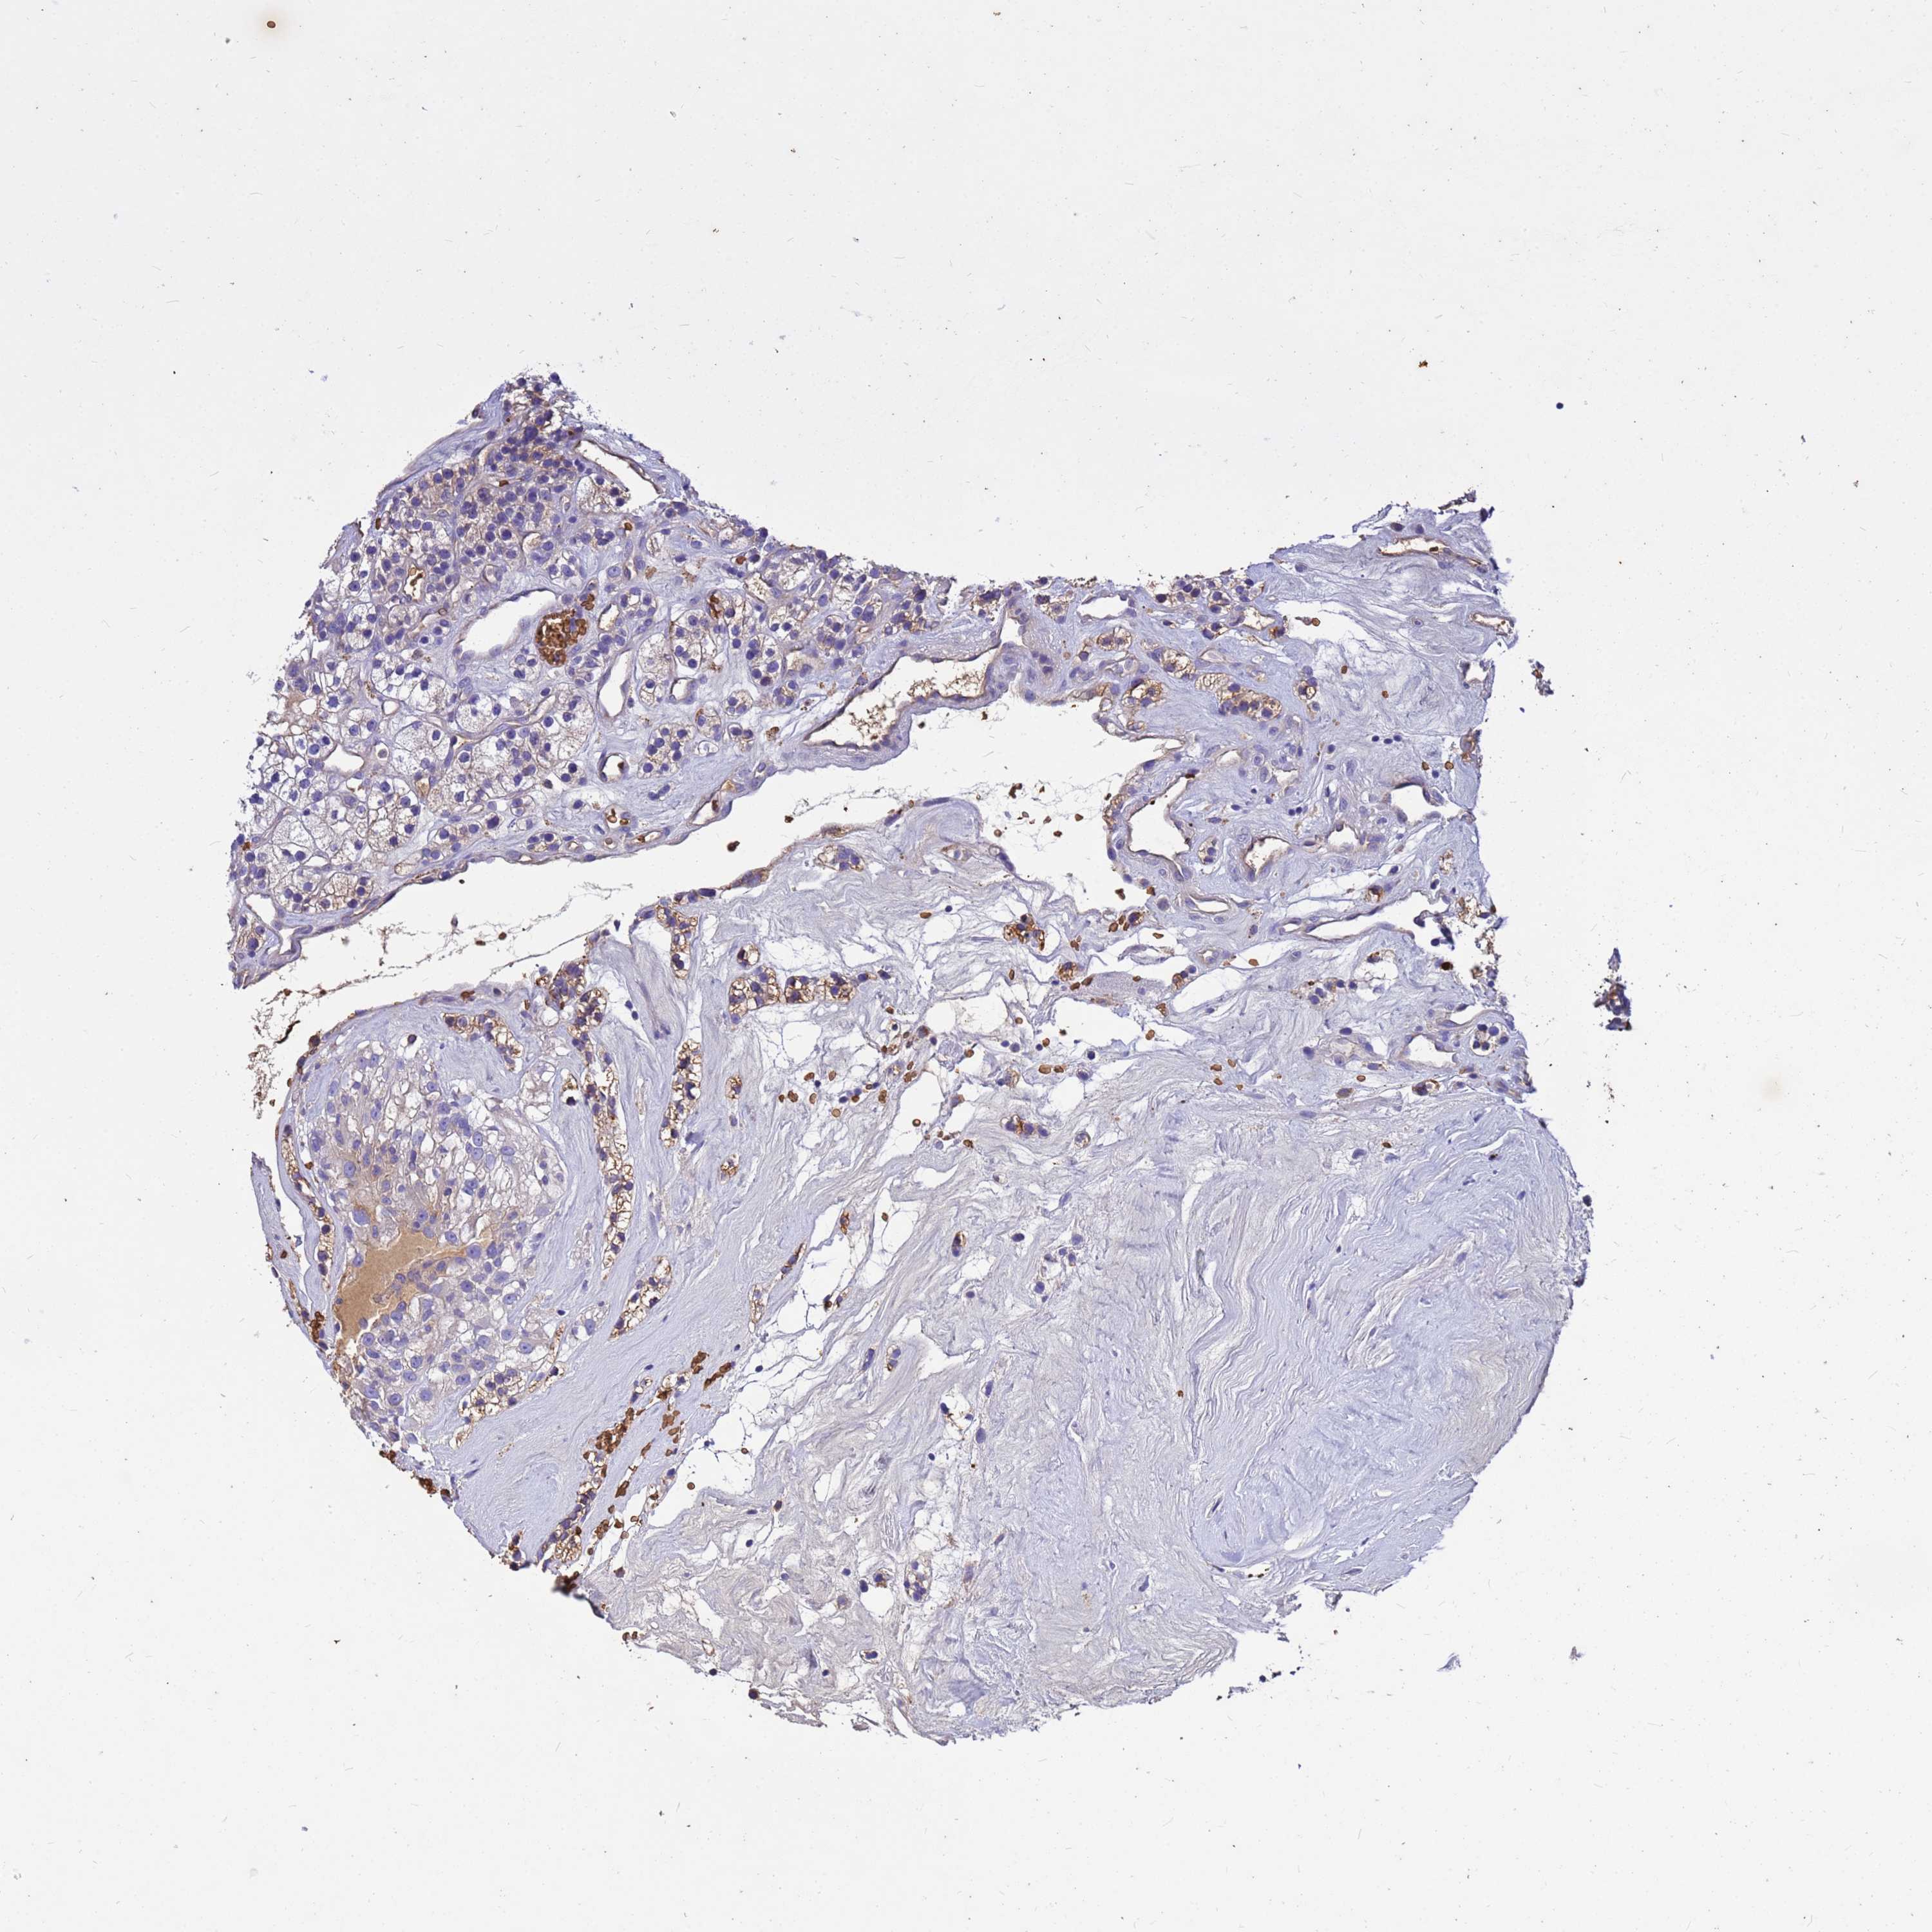

KIDNEY RENAL CLEAR CELL CARCINOMA (VALIDATION) - Interactive survival scatter ploti

The Survival Scatter plot shows the clinical status (i.e. dead or alive) for all individuals in the patient cohort, based on the same data that underlies the corresponding Kaplan-Meier plots. Patients that are alive at last time for follow-up are shown in blue and patients who have died during the study are shown in red.

The x-axis shows the expression levels (FPKM) of the investigated gene in the tumor tissue at the time of diagnosis. The y-axis shows the follow-up time after diagnosis (years). Both axes are complimented with kernel density curves demonstrating the data density over the axes. The top density plot shows the expression levels (FPKM) distribution among dead (red) and alive patients (blue). The right density plot shows the data density of the survived years of dead patients with high and low expression levels respectively, stratified using the cutoff indicated by the vertical dashed line through the Survival Scatter plot. This cutoff is automatically defined based on the FPKM cutoff that minimizes the p-score. The cutoff can be changed by dragging the vertical line or by entering a cutoff value in the square labeled "Current cut-off".

Under the Survival Scatter plot the p-score landscape (black curve; left axis) is shown together with dead median separation (red curve; right axis). Dead median separation is the difference in median mRNA expression between patients who have died with high and low expression, respectively. It is calculated as follows: median FPKM expression of dead patients with high expression - median FPKM expression of dead patients with low expression. This is intended to aid the user in visually exploring custom cutoffs and the associated p-scores and dead median separation.

Individual patient data is displayed and can be filtered by clicking on one or more of the category buttons on the top of the page. Categories describing expression level and patient information include: high, low, alive, dead, female, male and tumor stages. The scale of the x-axis can be toggled between linear and log-scale by clicking on the "x log" button. Mouse-over function shows TCGA ID, patient information and mRNA expression (FPKM) for each patient.

& Survival analysisi

Kaplan-Meier plots summarize results from analysis of correlation between mRNA expression level and patient survival. Patients were divided based on level of expression into one of the two groups "low" (under cut off) or "high" (over cut off). X-axis shows time for survival (years) and y-axis shows the probability of survival, where 1.0 corresponds to 100 percent.

HBA1 is not prognostic in Kidney Renal Clear Cell Carcinoma (validation)

Best expression cut offi

: 41.01

Average pTPM 72.8

Number of samples 100